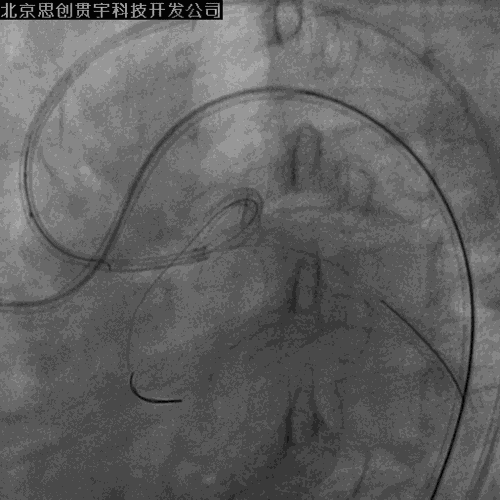

LCX-逆向PCI

PL-左房支-LCX侧枝

Corsair+SION

IVUS引导下UB3+corsair微导管进入正向指引

穿微导管技术送LCX导丝( Modified Rendezvous )